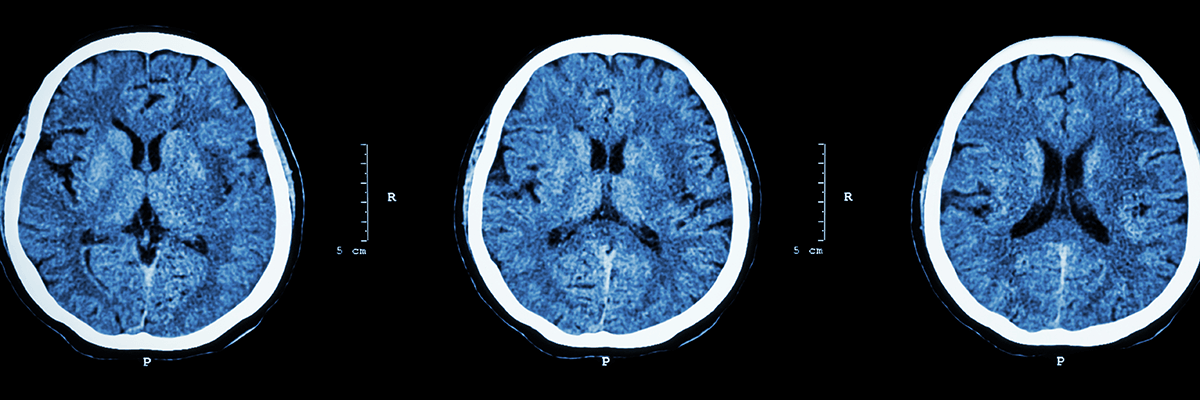

Welcome to the Willis Knighton Neurovascular Institute